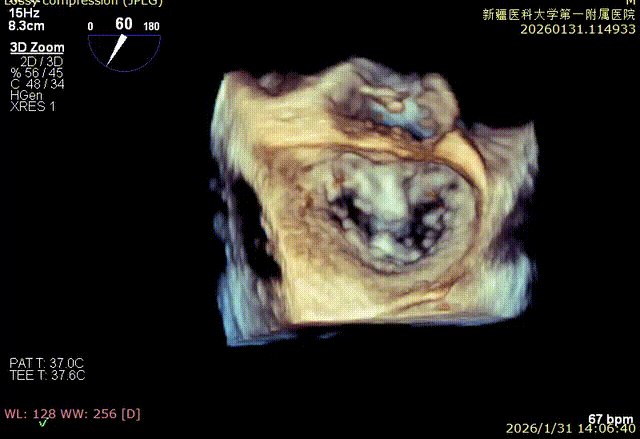

3D enface 切面

3D enface观察反流

3D enface 完成Orientation调整

3D enface反流充分降低

3D enface 观察后叶栓系